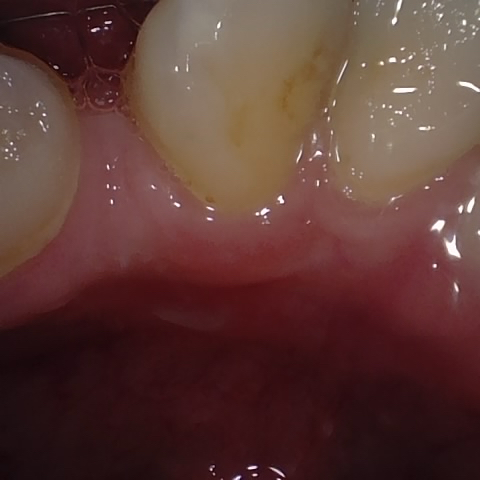

Image 59 / 400

NHD20794

Annotated as "Bad"

Original Image Rendering Image